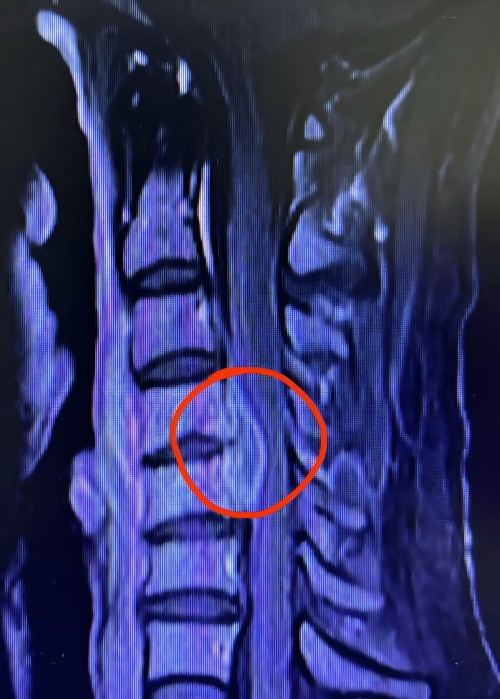

患者颈椎磁共振(MRI)显示椎管内有大量脓液

然而,离手术仅差两小时,患者突然出现乳头平面以下感觉消失,四肢瘫痪,不能活动。刘斌医生在得知患者病情变化后立即赶往医院与向铁城医生为患者行急诊手术,手术非常顺利。术中在患者颈椎椎管内发现了大量脓液,严重压迫脊髓,这正是造成患者瘫痪的元凶。手术彻底清除了脓肿,解除了其对脊髓的压迫。手术虽顺利完成,但刘斌副主任医师仍然不放心,一直在术后复苏室等候患者清醒,以便在第一时间观察患者神经功能恢复情况。值的庆幸的是,患者麻醉清醒后即感觉轻松不少,四肢出现不同程度的活动。刘斌副主任医师随即松了一口气,他说只要术后有恢复就有完全康复的希望。术后第四天,患者四肢功能基本恢复正常。